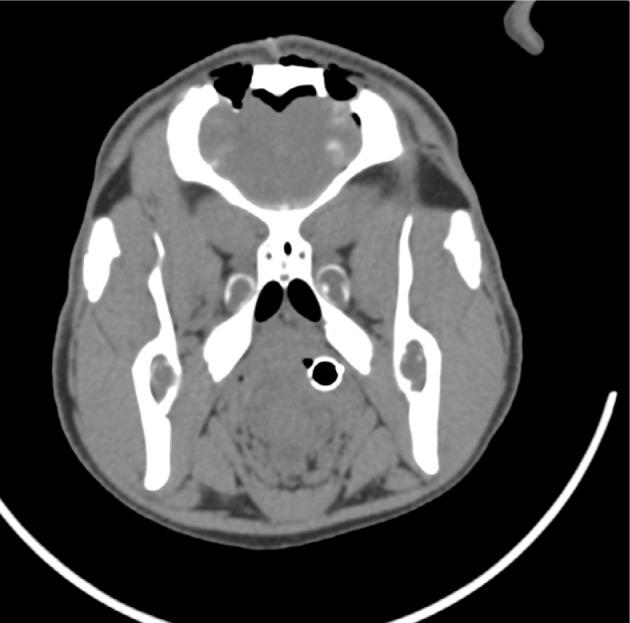

The prototype needle selected was 1.66 mm in diameter, with bevel angle of 10° and fillet radius of 0.25 mm. Upon examination of postoperative CT and histological images, no differences in tissue trauma or hemorrhage were noted between the prototype needle and the Sedan needle.

所选的原型针直径为1.66mm,斜角为10°,圆角半径为0.25mm。在检查术后CT和组织学图像时,未发现原型针和Sedan针在组织创伤或出血方面存在差异。